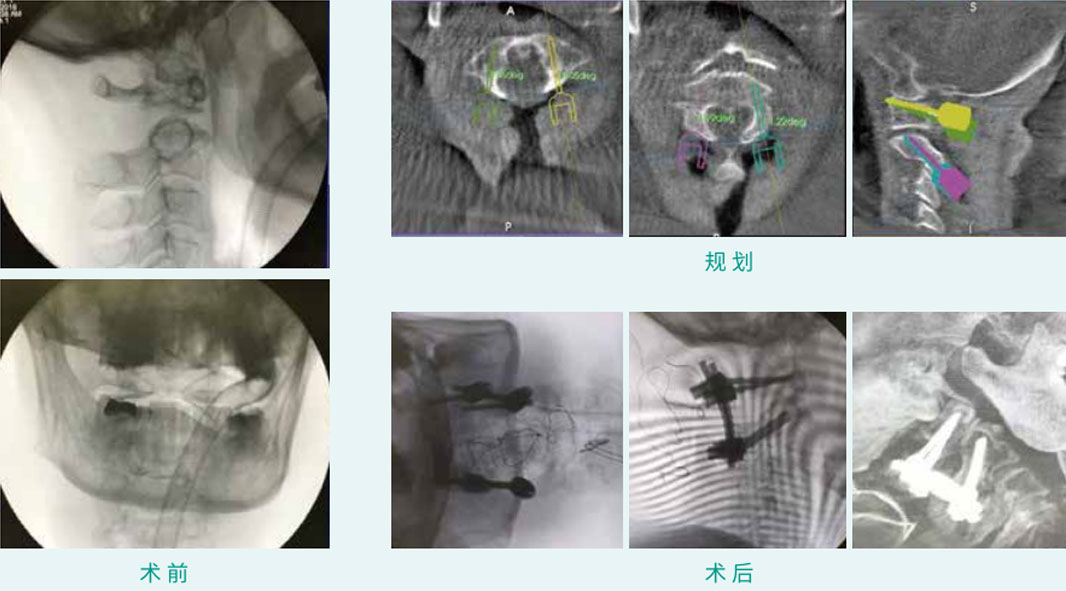

天玑? 辅助寰枢椎椎弓根螺钉内牢靠术

基本情形:患者女,,,,,,65岁,,,,,,寰枢椎脱位

机械人累积用时:35分钟

植入物:4枚椎弓根螺钉

病例泉源:广东省中医院 林定坤 陈博来 李永津